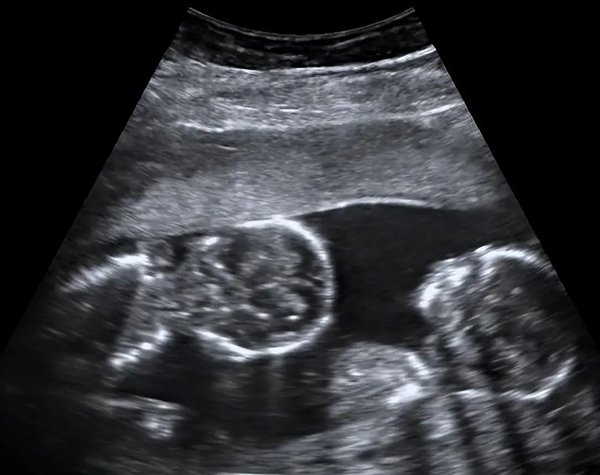

2020年10月,凯莉在医院查出来怀了双胞胎,非常开心,为了孩子能健康生长,她按时去医院体检。

一般来说,可以延迟出生的双胞胎,有2个胎盘,2个羊膜囊,所以一个胎儿出生后,并不会影响其他胎儿继续发育。